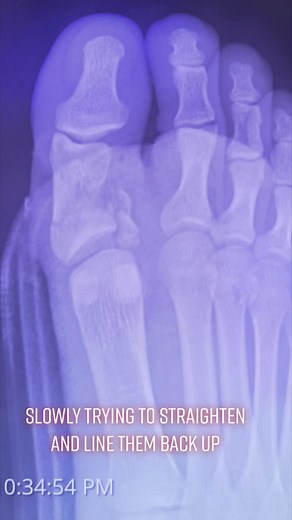

Slow process to straighten and line the bones up

已浏览 8959 次

2022年10月4日

TikTok

jamescrowl